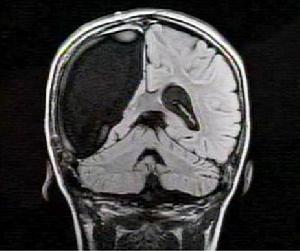

腦電圖檢查可見一側半球,特別是顳葉局灶性δ波,有癎樣放電,但有時腦電圖正常。頭顱MRI檢查,可見腦室擴大,一側島葉和島周圍區擴大,皮質和皮質下異常信號,重則半球萎縮伴同側尾核頭部萎縮。

2、磁共振成像(MRI)和正電子發射計算機斷層掃描(PET):所有患者均有2次以上的MRI檢查,病變部位主要在顳葉、額葉的灰質及灰白質交界處。12例患者為一側半球皮層的進行性萎縮;1例(No.4)患者雙側半球皮層均有萎縮,以左側半球為主。4例患者在行PET檢查,可見患側半球表現為瀰漫性低代謝改變。

MRI表現為一側半球皮質的進行性萎縮,在本組的每個病例均表現的非常明顯。ChiappariniL曾詳細描述了RE的MRI特點。在發病最初的4個月內,大部分患者表現為島葉或外側裂區域的間隙擴大,皮質或皮質下(T2/FLAIR)信號增高,同側尾狀核頭部信號增高;而少部分患者可表現為局灶性皮質腫脹。隨後,在受累側半球則會出現以島葉、外側裂為中心,向周圍皮質擴散的進行性萎縮和擴大的異常信號範圍。但是,也曾觀察到少數病例的患側半球皮質無進行性萎縮的情況,儘管有典型的臨床症狀學表現。